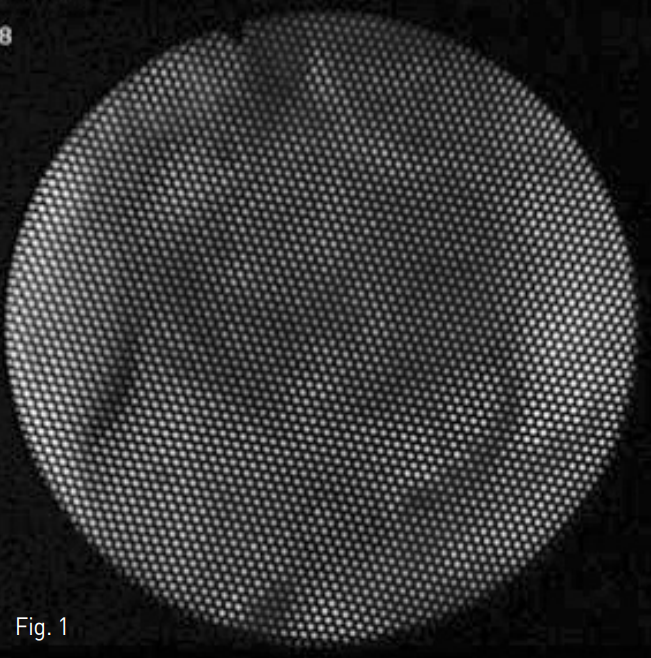

환자는 우측 대퇴동맥을 천자하여 6 Fr Flexor Check Flo introducer (COOK Incorporated., Bloomington, US) 를 삽입하고 sheath를 오른쪽 신장동맥의 기시부에 거치시켰다. 동맥 조영술을 시행하여 오른쪽 신장 실질에 조영제의 혈관 외 유출 혹은 과혈관성 종양 등의 이상은 보이지 않았다 (Fig. 3).

Fig. 3

Right renal artery angiography shows no detectable abnormality in right kidney.